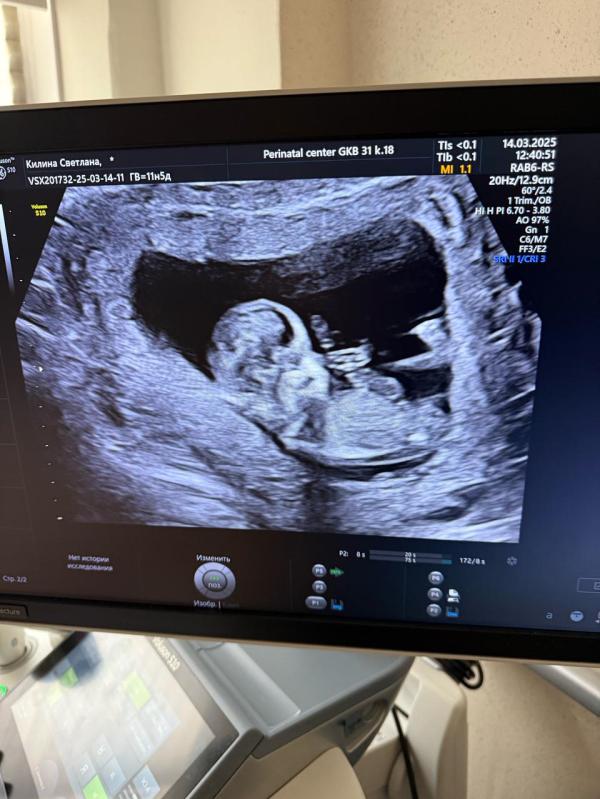

Девочки🌸 у кого есть опыт , можно предположить по фото, кого ждем? Срок по узи 12,3) врач сказала, что это не точно, но она предполагает, что мальчик🙈 третий парень🙈 я то готова, муж грустит)))

@ekaterinade, ну как знаете ) работаю уже не год и не два пренатальным диагностом) видеть можно все, что угодно) но поверьте ,иногда очевидный мальчик оказывается девочкой) на 1 скрининге. Да мы можем почти на 90 процентов озвучить пол при идеальном положении плода - но никак не потому что видим половые губы или половой член )

@gdzhst, а по каким тогда признакам озвучивается пол ??? Я конечно понимаю , что на этом сроке видно «половой бугорок» а не полностью развитые половые органы…но ведь исходя из его внешнего вида и делается предположение , не так ли?

@ekaterinade, исключительно исходя из его наклона. Который при несколько косом положении плода, либо если он слишком согнут - может быть не очень достоверным. Иногда я вижу у меня плод лежит идеально, я озвучиваю сразу что я практически уверена , но иногда бывали случаи когда кажется что мальчик , при этом я понимаю что плод лежит ну так себе) , а потом к концу исследования оказывется уже что девочка

Вот я не могу этот угол наклона рассмотреть, ни на фото, ни на видео, которое еще сняли

@brenlanda, как все пишут- фото не информативно, полностью согласна))

До 20 недели каждая 2я девочка как мальчик 😂 рано предполагать ) а фото промежность и гениталии не передает)